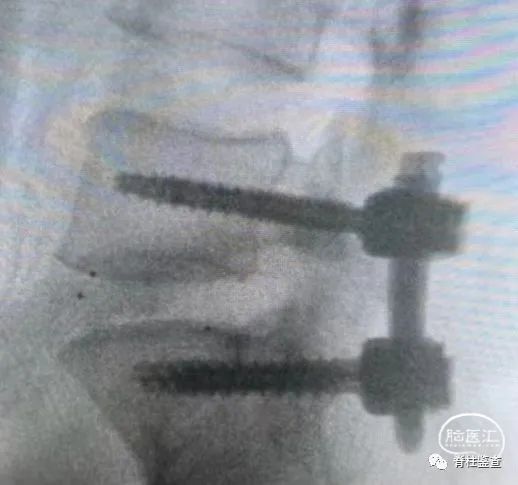

置入椎弓钉螺钉

置入长度及弯度适中的钉棒

腰椎滑脱

腰4-5退变性滑脱+椎管狭窄